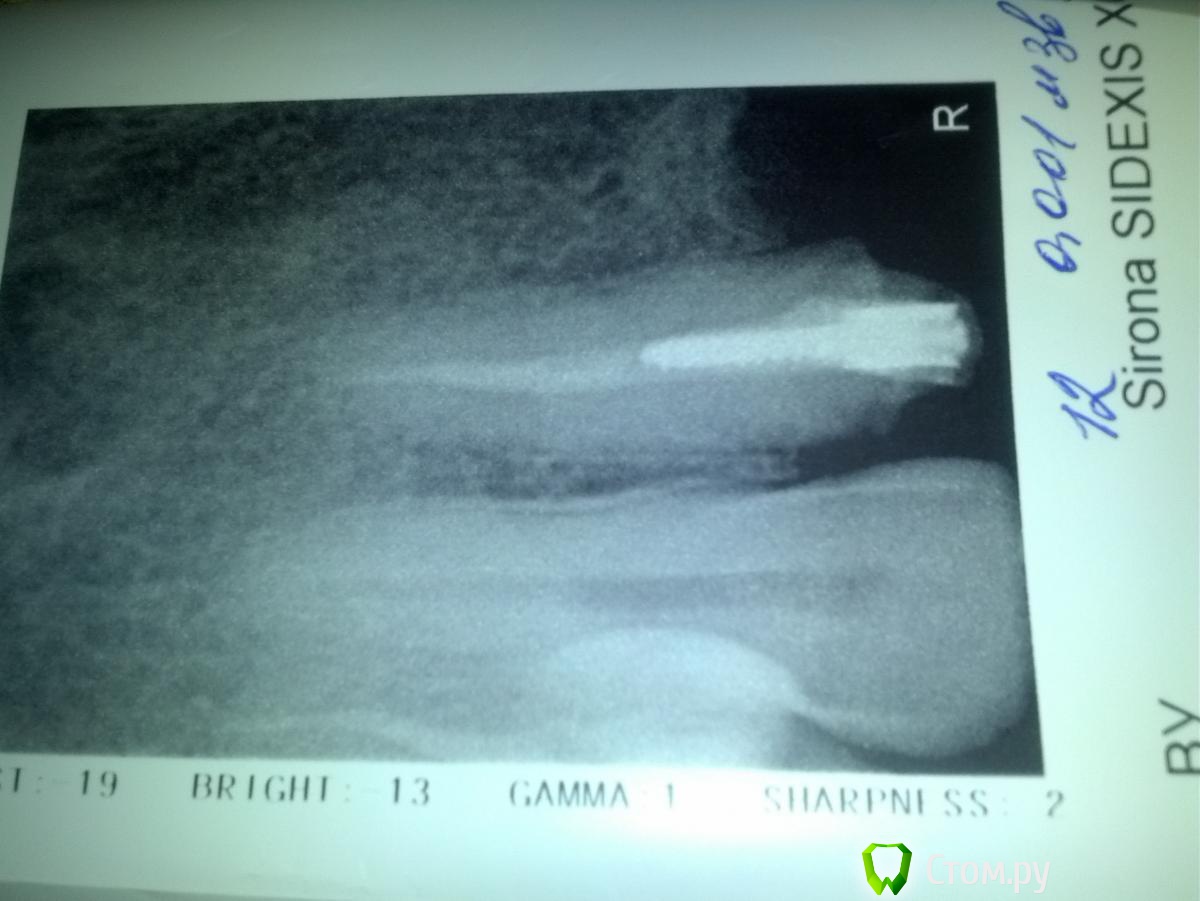

Занялась передними зубами, одного центрального резца нет, собираюсь поставить цирконий на 4 резца и клык. Сейчас возник вопрос, как лучше подготовить зубы под цирконивые коронки, если от зубов по сути остались только корни: 20 лет назад ставила пластик-сточили очень сильно (причем депульпировала здоровые зубы для эстетики :() , 11 лет назад поменяла на металокерамику, пришлось наращивать, сейчас меняю из-за синеватой полоски на уровне десны(показался метал) ...Сейчас врач просит нарастить еще для циркония, и поменять пломбы (судя по реакции терапевта-там одни пломбы и остались, коронковой части как таковой нет..врач-ортопед за стекловолоконные штифты (амортизируют лучше-говорит), терапевт, говорит, что лучше вкладок ничего не может быть, при таких разрушениях и что стекловолокно потом не достать..Хочу сделать отдельные коронки (ну кроме моста с отсутствующим резцом)..посоветуйте, пжл.что сделать:вкладки или стекловолокно... Сейчас в зубах стоят металлич.штифты (кроме одного, который сегодня вытащили и пока ничего не поставили)..К консенсусу ортопед и терапевт придти не могут, решение оставили за мной.